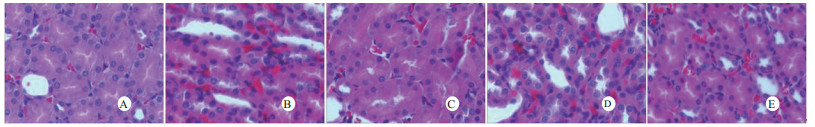

光镜下可见,假手术组肺泡大小形态均匀,结构清晰,肺泡腔内无出血和白细胞浸润;感染性休克组肺泡壁破坏严重,血管壁和肺泡间隔明显增厚;U50488H+感染性休克组大部分肺泡腔均匀一致,肺间隔略增厚,肺泡壁轻度水肿,但出血和白细胞浸润情况比感染性休克组明显减轻(图 1)。假手术组心肌细胞大小一致,排列整齐,核浆比正常,心肌细胞核呈椭圆型,胞浆均匀红染;感染性休克组心肌细胞肿胀,体积明显增大,细胞核大而异型,核内染色质固缩、边集,白细胞浸润明显增加;U50488H+感染性休克组多数心肌细胞形态相对正常,少数心肌细胞呈现脂肪变性(图 2)。假手术组肝细胞结构完整,肝小叶形态正常;感染性休克组肝细胞显著肿胀、呈空泡样和点状/小片状坏死;U50488H+感染性休克组肝细胞轻度肿胀,未见明显坏死灶、肝血窦扩张和炎性细胞浸润(图 3)。假手术组肾组织结构大致正常;感染性休克组肾小管细胞轻度水肿、空泡变性;U50488H+感染性休克组肾小管形态大致正常,间质无明显出血水肿(图 4)。

| A:假手术组,B:感染性休克组,C:U50488H+感染性休克组,D:nor-BNI+U50488H+感染性休克组,E:nor-BNI+感染性休克组 图 4 U50488H对感染性休克肾组织形态的影响(HE×400) Fig 4 Histopathological features of kidney(HE×400) |

扫描电镜下可见,假手术组肺泡形态完整,肺泡壁光滑;感染性休克组肺泡明显压缩畸形,肺泡隔肿胀、扭曲、隆起;U50488H+感染性休克组肺泡形态大致完整,少数肺泡壁肿胀受损(图 5)。透射电镜下可见,假手术组心肌细胞形态正常;感染性休克组心肌细胞溶解、坏死、肌纤维断裂;U50488H+感染性休克组心肌细胞大致正常,无明显坏死(图 6)。假手术组肝细胞形态正常,毛细胆管未见扩张;感染性休克组肝细胞大片坏死,毛细胆管明显扩张;U50488H+感染性休克组肝细胞形态大致正常,毛细胆管略扩张(图 7)。假手术组肾小管上皮细胞形态狭长,核卵圆形,位于基底部;感染性休克组肾小管上皮断裂,微绒毛缺失;U50488H+感染性休克组肾小管上皮细胞大致正常,微绒毛不平滑,但无明显坏死(图 8)。

| A:假手术组,B:感染性休克组,C:U50488H+感染性休克组,D:nor-BNI+U50488H+感染性休克组,E:nor-BNI+感染性休克组 图 8 肾组织透射电镜检查(×15 000) Fig 8 Transmission electronic microscopic photos of kidney(×15 000) |

本研究还进一步观察了感染性休克大鼠重要脏器的病理学变化与超微结构。结果发现,感染性休克时,肺泡壁破坏严重,血管壁和肺泡间隔明显增厚,炎症细胞浸润较多,肺泡明显压缩畸形,肺泡隔肿胀,扭曲,隆起。该结果与潘景业等的报道一致。同时实验发现,U50488H可减轻感染性休克肺泡壁出血水肿与肺组织炎性细胞浸润,抑制肺间隔增厚。实验还观察到感染性休克大鼠心肌纤维肿胀、扭曲、断裂、溶解,并由此导致心功能障碍。U50488H亦可减轻线粒体肿胀崩解和心肌细胞溶解与坏死,可能与U50488H减轻心肌抑制有关[12],具体机制与分子通路尚需进一步实验验证。本研究还观察到感染性休克大鼠肝细胞出现肿胀、空泡样脂肪变性和点状/小片状坏死,毛细胆管明显增多、扩张;肾小管细胞轻度水肿、空泡变性,肾小管上皮细胞微绒毛缺失,细胞崩解,肾小管上皮断裂。预先给予U50488H可显著减轻感染性休克肝细胞浊肿、肝血窦扩张和炎性细胞浸润;抑制肾小管上皮细胞核变形、微绒毛坏死和间质出血水肿。nor-BNI可阻断这一效应。上述结果均提示U50488H可通过激动κ-阿片受体,改善肝脏和肾脏血流量保护感染性休克肝脏和肾脏功能,具体机制可能和细胞凋亡等相关。